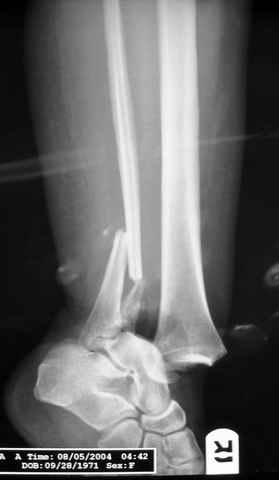

Pilon fracture:

-Появляется ориентир и остов, на чем можно строить восстановление, почему сперва малоберцовую, впервые обьяснили и описали (Pylon type and Ankle fractures) в середине 50х Rienau и Gay.

Восстановливая длину и ротацию малоберцовой кости, затем относительно легче произвести реставрацию остальных элементов перелома дистального эпиметафиза болшеберцовой кости.

где исследования на трупах показали, что малоберцовая кость участвует в стабильности голеностопного сустава, поддерживая наклон тарана (talar tilt) за счет связок. После ознакомления работой Ramsey в ортопедию ввели термин "при переломах голеностопного сустава смещенная

таранная кость следует за малоберцовой костью" т.е. связка не рвется, а тянет таран за собой, поэтому восстановление малоберцовой кости в

первую очередь, затем остальных элементов - стал классическим при лечении данной патолгии. Латеральная колонна (столб), дистальный

конец малоберцевой кости, к нему прикрепляется латеральный суставной фрагмент дистального эпиметафиза большеберцовой кости (как на снимке)

и таранная кость, которые при репозиции малоберцовой кости репонируются автоматически.

При косых переломах малоберцовой кости применение пластин отличается от обычных, показание antiglade technique-методика против скольжения, потому что укорочение длины малоберцовой кости чреваты ранними артрозами.

Из работ Ramsey and Hamilton, Yablon et., укорочения на 1мм

малоберцовой кости, уменьшает на 42% контактную поверхность между

малоберцевой и таранной кости, которое в свою очередь приводит к

увеличению давления на остальные части суставной поверхности, что

является предпосылкой раннего артроза.